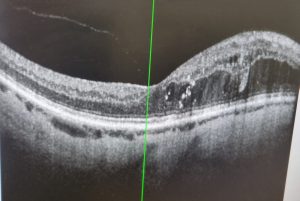

If left untreated this damage will eventually lead to loss of vision and eventually blindness. Getting DR diagnosed as early as possible is important as, like most disorders, it is easier to treat in the early stages. Getting blood sugar under control is crucial in the treatment of DR. Even when treated the condition may lead to the development of macular oedema (edema in American English). Basically a build up of fluid in the part of the eye known as the macula. This is the part of the eye that process what you see directly in front of you. The macula lets you see small details and focus on very specific aspects of what you’re looking at. The image below shows a retinal scan showing macula oedema. I took this picture from the original scan that the opthalmologist showed me. This was my right eye in September 2025. The green line is the centre of the eye, the bulge to the right is the oedema. Macula oedema can affect you vision particularly when reading or trying to study fine details. It can also make your vision blurry. To date mine hasn’t got to that stage, hopefully it never will.